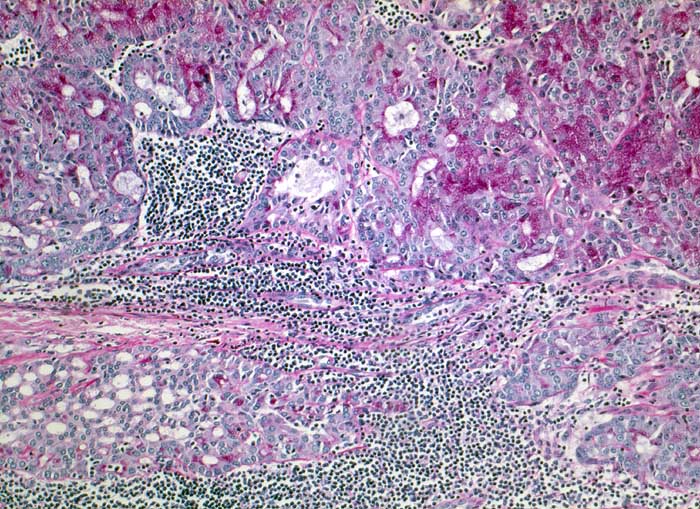

p/ Azinuszellkarzinom der Glandula Parotis

Azinuszellkarzinom der Glandula Parotis

Die zytologische Diagnose des Azinuszellkarzinoms basiert auf dem Nachweis von Azinuszellen bei gleichzeitigem Fehlen von Gangstrukturen. Die Tumorzellen gleichen normalen serösen Azinuszellen. Zytoplasma ist reichlich vorhanden und variiert von schaumig bis grobgranulär. Degranulierte Zellen erscheinen schaumig, Zellen mit dichtgepackten Granula gleichen Onkozyten. Die Granula der Onkozyten sind aber feiner. Die Tumorzellkerne sind meist ziemlich wenig atypisch und monomorph. Das Chromatin variiert von fein bis mittelgrob. Intranukleäre Zytoplasmaeinschlüsse kommen vor. Die oft vorhandenen zahlreichen Nacktkerne müssen von ebenfalls oft vorhandenen Lymphozyten abgegrenzt werden. Die meist hoch differenzierten Tumoren können mit normaler Speicheldrüse verwechselt werden.